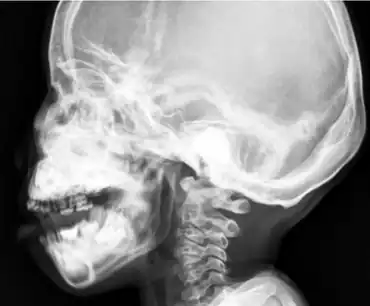

Sclerosis and hyperostosis of the skull base, maxilla, and mandible.

Craniometaphyseal dysplasia is diagnosed based on clinical and radiographic findings that include hyperostosis. Some things such as cranial base sclerosis and nasal sinuses obstruction can be seen during the beginning of the child's life. In radiographic findings the most common thing that will be found is the narrowing of foramen magnum and the widening of long bones. Once spotted treatment is soon suggested to prevent further compression of the foramen magnum and disabling conditions.